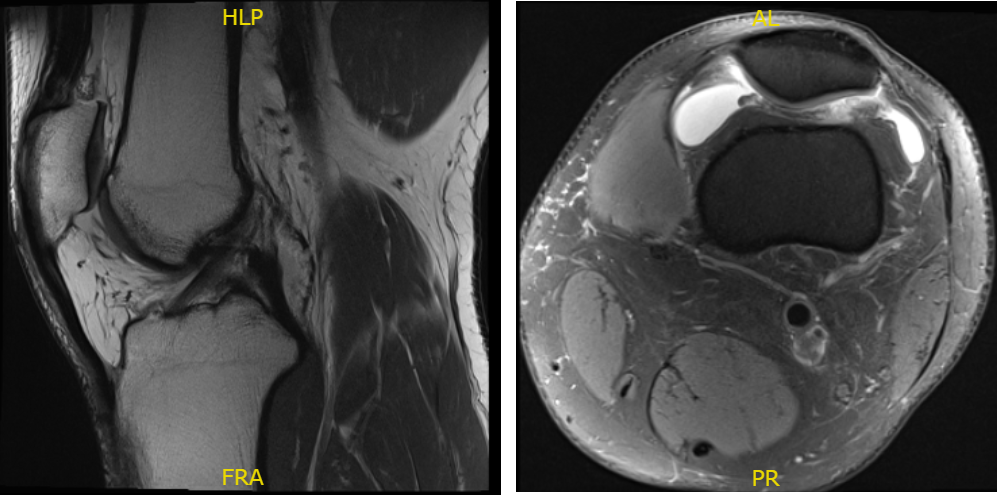

Fig. 1 MRI of the left knee in sagittal and coronal sections.

There is no acute fracture or osteonecrosis however there is mild patellofemoral compartment cartilage wear and a complex tear of the medial meniscus involving the body and posterior horn.

There is a focal full-thickness cartilage fissuring overlying the lateral trochlea with mild reactive subchondral edema. The tear demonstrates a predominant longitudinal component within the posterior horn. Additional horizontal oblique tearing is noted with free edge margin fraying.

Mild reactive edema is present within the subjacent medial tibial plateau. The posterior root attachment is intact. There are no full-thickness cartilage defects. There is a moderate joint effusion. A very small popliteal cyst is present. There are no intra-articular ossific loose bodies.